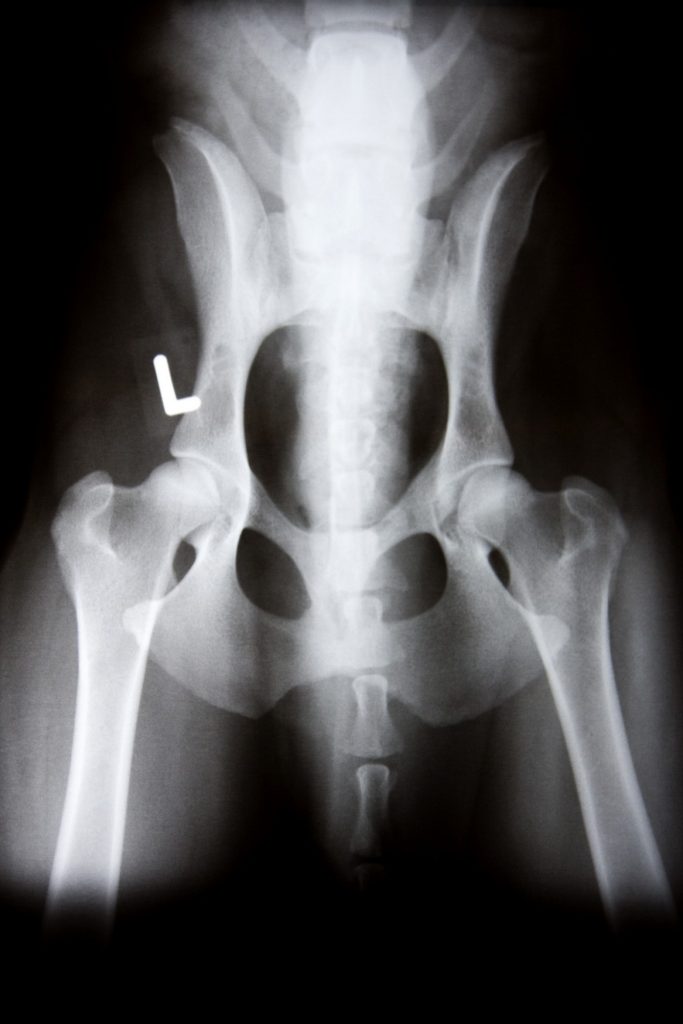

Digital radiology allows us to safely and non-invasively view your pet’s internal organs, bones, and tissues. X-rays are an essential diagnostic tool in detecting injuries, tumors, or illnesses early. Our trained staff ensures your pet receives the highest level of care during every radiology procedure.